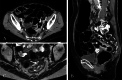

Case presentation: A 71-year-old woman presented to our hospital with bloody stools. A colonoscopy revealed type 2 advanced cancer in the rectum, and a histological examination exposed a well-differentiated adenocarcinoma. Abdominal enhanced computed tomography divulged rectal wall thickening without significant swelling of the lymph nodes or distant metastasis. Pelvic magnetic resonance imaging showed tumor invasion beyond the intrinsic rectal muscle layer. The patient was diagnosed with cStage IIa (cT3N0M0) rectal cancer and underwent low anterior resection using the hinotori™ Surgical Robot System. Based on an adequate simulation, surgery was safely performed with appropriate port placement and arm base-angle adjustment. The operating time was 262 min, with a cockpit time of 134 min. Subsequently, the patient was discharged 10 days postoperatively without complications. The pathological diagnosis was pStage IIA (cT3N0M0) and the circumferential resection margin was 6 mm.